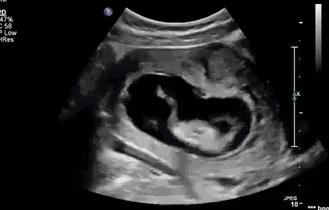

在怀孕到四个月的时候,准妈妈们大多都会感到胎动,后面会越来越明显,变成这种:

其实小家伙很小的时候就已经开始“闹腾”了:妥妥的一个运动健将!

小碎步向前缩,撅着小屁股用力一蹬,身体向后滑去——“母胎版蛙泳”动作很标准嘛!